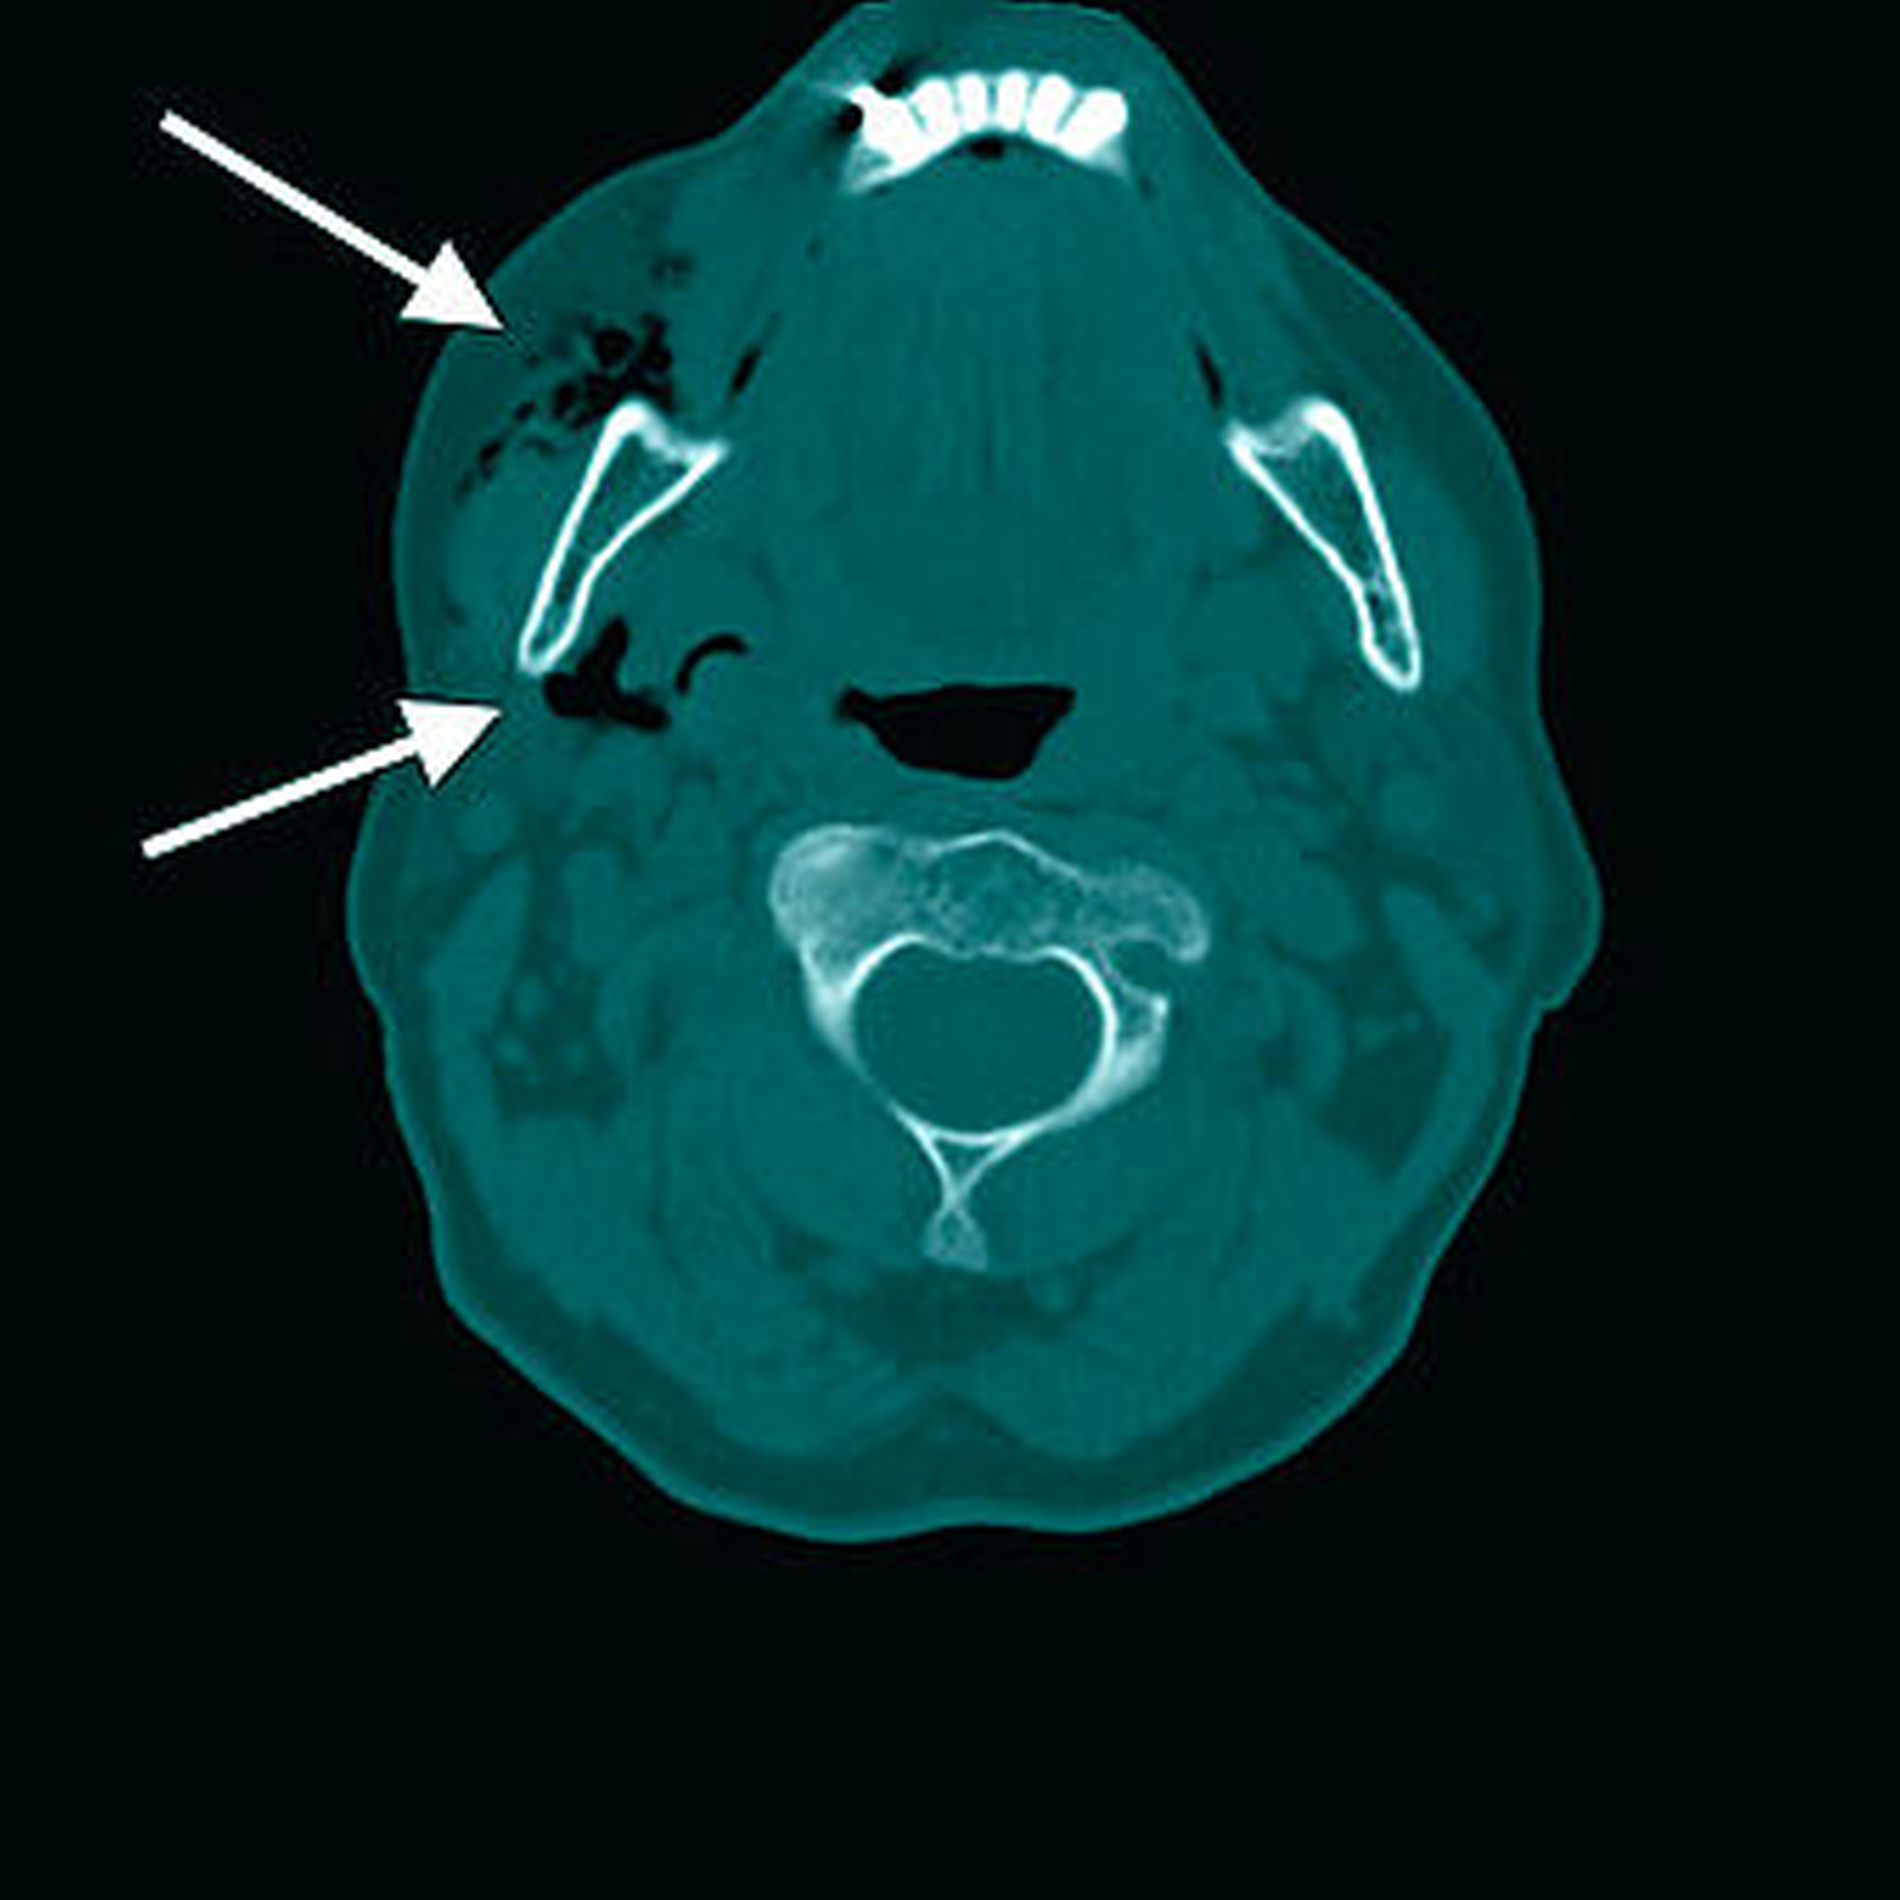

Bei der klinischen Untersuchung klagte der Patient über inspiratorische Schmerzen in der linken Thoraxhälfte. Die manuelle Palpation der linksseitig lokalisierten Schwellung im Gesichts und Halsbereich (Abbildungen 1 a und b) zeigte ein für das Weichteil- emphysem typisches druckdolentes spür- und hörbares Knisterrasseln. Die durchgeführte Nativ-CT-Untersuchung von Kopf, Hals und Thorax erbrachte ein ausgeprägtes Weichteilemphysem mit Ausdehnung von der Temporalregion über die beidseitige Zervikalregion bis ins Mediastinum (Abbildungen 2a bis d).

In der durchgeführten CT-Untersuchung von Kopf und Hals zeigte sich auch hier ein Weichteilemphysem mit Ausdehnung von der rechten Wange bis in die zervikalen Bindegewebslogen (Abbildungen 4a bis c). Auch in diesem Fall wurde eine stationäre Aufnahme zur Beobachtung sowie Einleitung einer i.v.-antibiotischen Prophylaxe-Therapie empfohlen und durchgeführt. Bei regredienter Schwellung und subjektivem Wohlbefinden konnte die Patientin drei Tage später beschwerdefrei zurück in die Häuslichkeit entlassen werden.